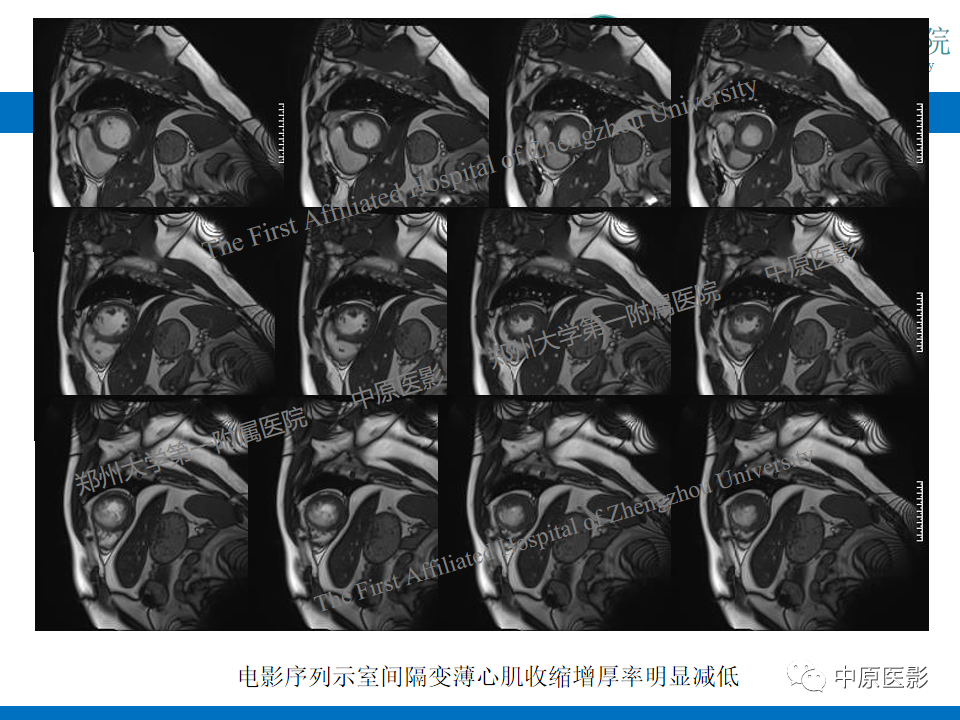

【病例】致心律失常性右室心肌病1例MR影像-4